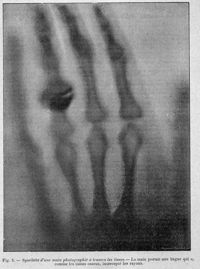

ImageSquelette d'une main photographiée à travers les tissus

-

ImageRadiographie de la main